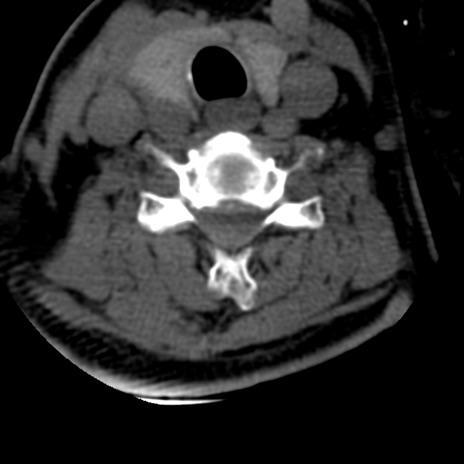

症例50 頚椎CT(横断像)

頚椎CT

冠状断像

矢状断像